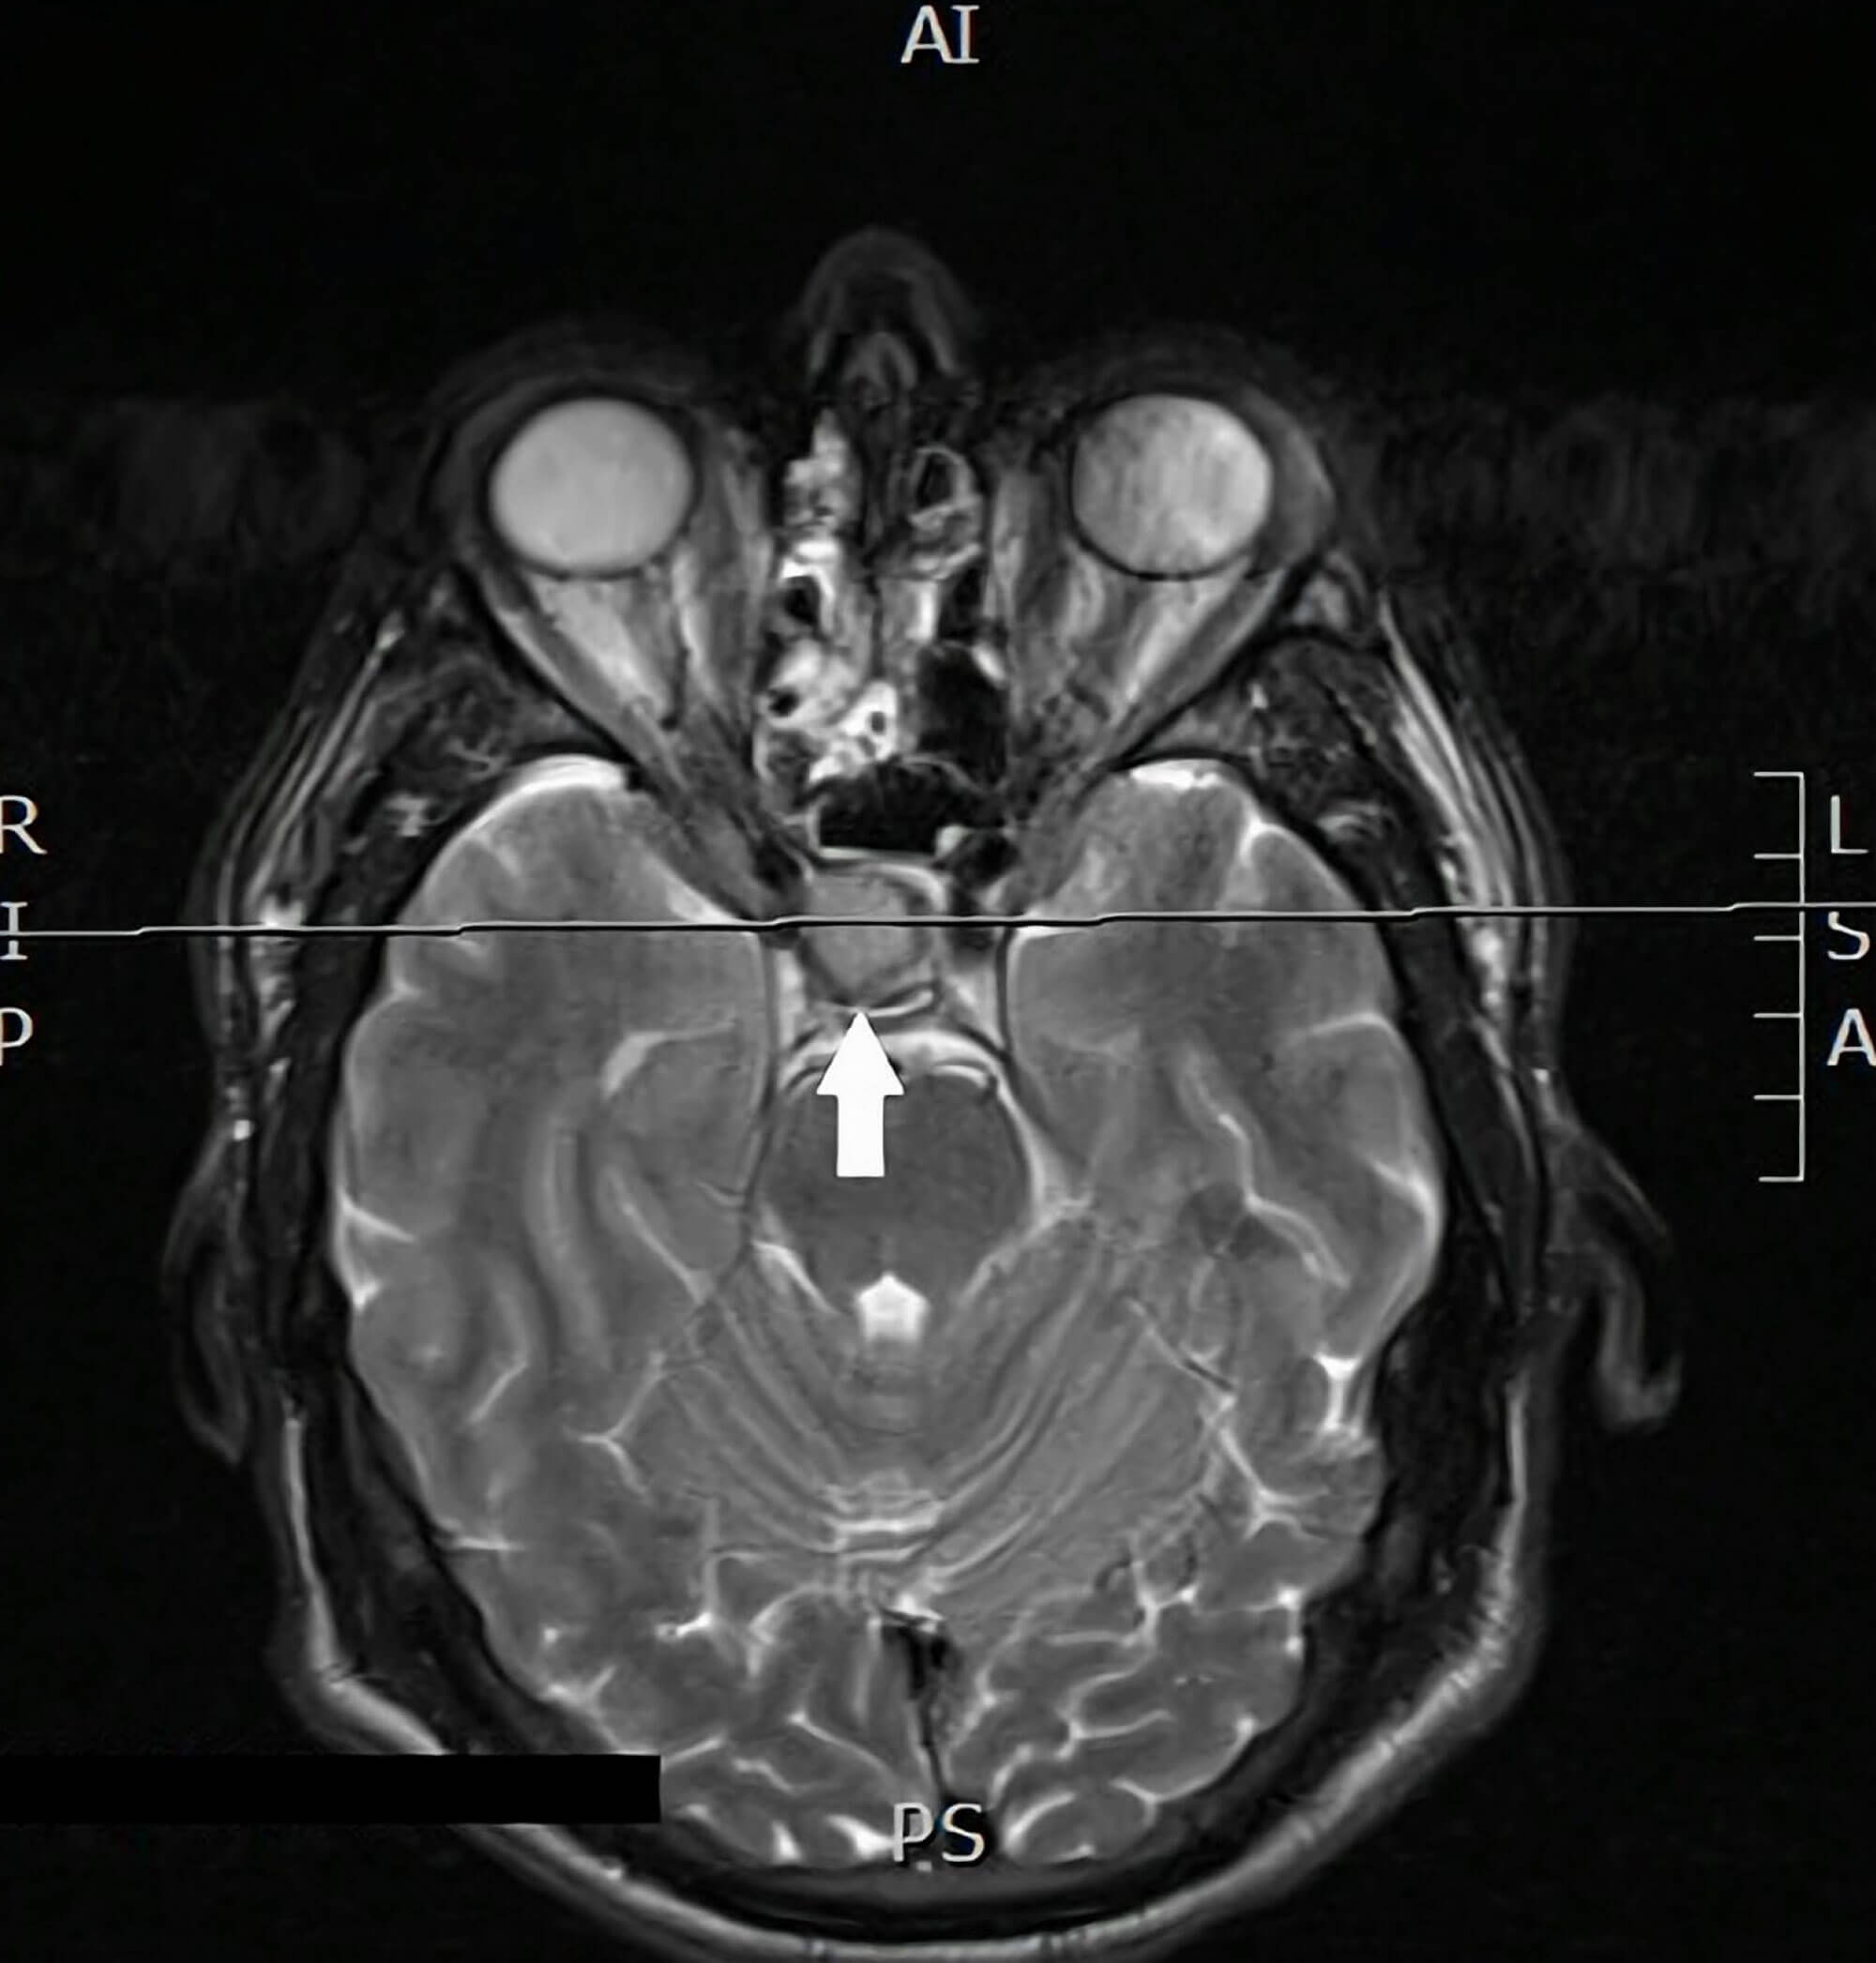

Figure 2: MRI head showing a well-defined sellar mass (15 x 15 x 17mm) with slight

suprasellar extension and mild elevation and compression of the optic chiasm.

Blood tests requested by the patient’s GP, in light of suspicions raised by the ophthalmologist, revealed a significantly raised insulin-like growth factor 1 (IGF-1), prolactin and glucose, with low testosterone. He was referred to the endocrinology team and MRI subsequently revealed a well-defined sellar mass (15 x 15 x 17mm) with slight suprasellar extension and mild elevation and compression of the optic chiasm (Figure 2). These findings were consistent with a growth-hormone secreting macroadenoma for which he was managed with pituitary surgery, after which his photophobia resolved.